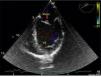

Primary cardiac tumors are rare in all age groups, with a reported prevalence of 0.001–0.03% in autopsy series. We report the case of a 37-year-old man, with no relevant medical history, who was admitted to the emergency department with sudden-onset right hemiparesis. Diagnostic studies revealed a small hypodense area in the left putamen and he was admitted to the stroke unit with a diagnosis of ischemic stroke. During investigation of the cause of stroke in such a young patient, he underwent transthoracic echocardiography, which showed a mass attached to the anterior leaflet of the mitral valve (Figure 1). Transesophageal echocardiography was then performed to clarify the picture, which confirmed a small echodense pedunculated mass, 0.5 cm2 in size, with well-defined borders, features typical of a fibroelastoma (Figures 2 and 3), attached to the atrial surface of the anterior mitral valve leaflet without causing mitral regurgitation (Figure 4). The rest of the echocardiographic examination revealed an estimated left ventricular ejection fraction of 65% and no other valvular abnormalities. The patient was subsequently referred to the cardiothoracic surgery center for surgical excision of the mass. Macroscopic examination showed a 0.6-cm whitish spiculated nodule with a soft elastic consistency. Histopathological study revealed cardiac myxoma. We present this case to highlight the unusual presentation, particularly its echocardiographic features.

Transesophageal echocardiogram in long-axis view, showing an echodense pedunculated mass adhering to the atrial face of the anterior mitral valve leaflet. The left atrial appendage can also be seen, with no evidence of thrombus. AAE: left atrial appendage; AE: left atrium; VE: left ventricle.